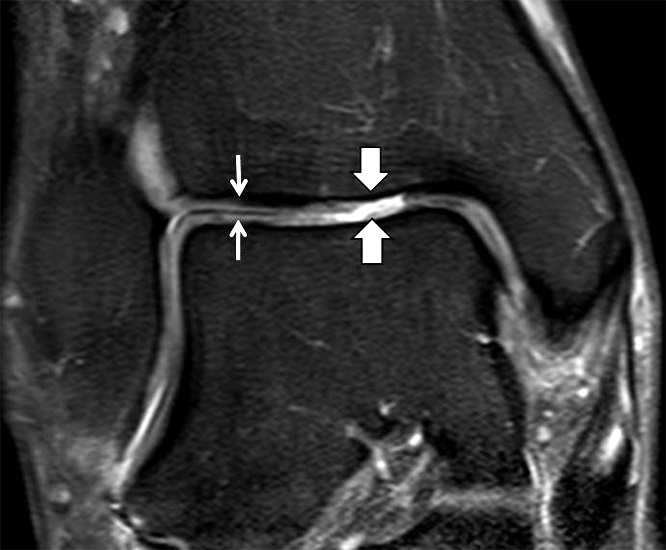

b. T2 fs axial. Infraktion des hinteren Volkmann‘schen Dreiecks (schmale, weiße Pfeile). Hier inserierende, intakte, hintere Syndesmose (breite, weiße Pfeile).

Abbildung 18b

Das Ligamentum tibiofibulare posterius (hintere Syndesmose) verläuft flacher und geht nach kranial in das Ligamentum tibiofibulare interosseus und nach kaudal in das Ligamentum intermalleolare posterius über. Letzteres bildet ein artikuläres Labrum zwischen Trochlea und Talus 9.

Da also die hintere Syndesmose an der posterioren Tibia inseriert, entspricht eine Fraktur oder Infraktion des hinteren Volkmann`schen Dreiecks funktionell einem knöchernen Ausriss des Ligamentum tibiofibulare posterius (Abb. 18 a und b). Aufgrund der Koinzidenz von Syndesmosenläsionen mit Innenbandverletzungen ist bei der Beurteilung gesondert auf solche zu achten.